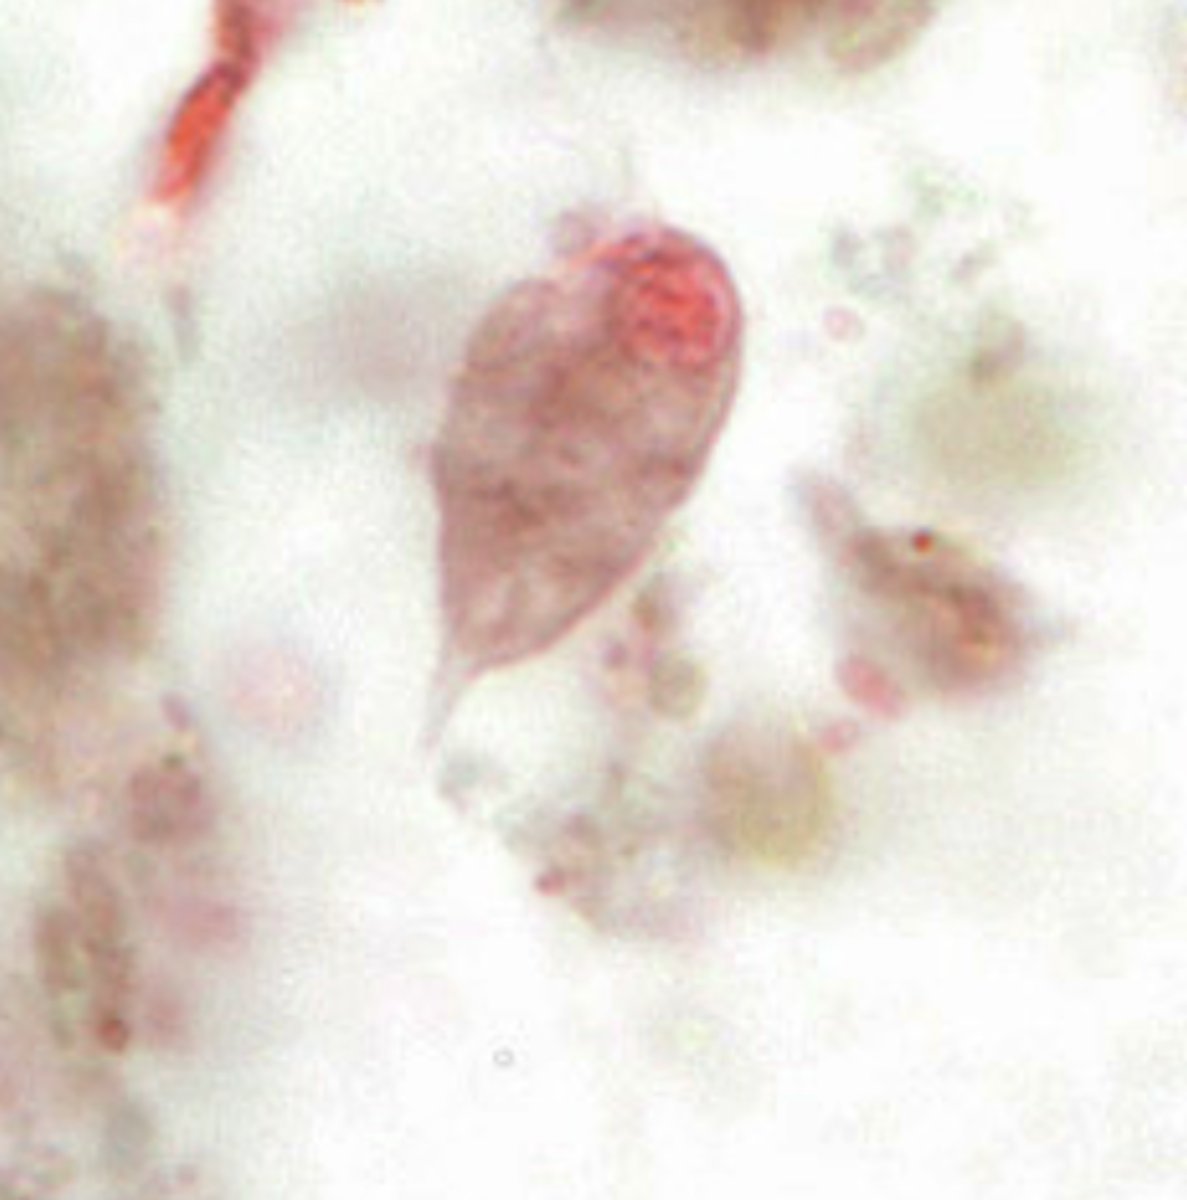

Giardia lamblia troph